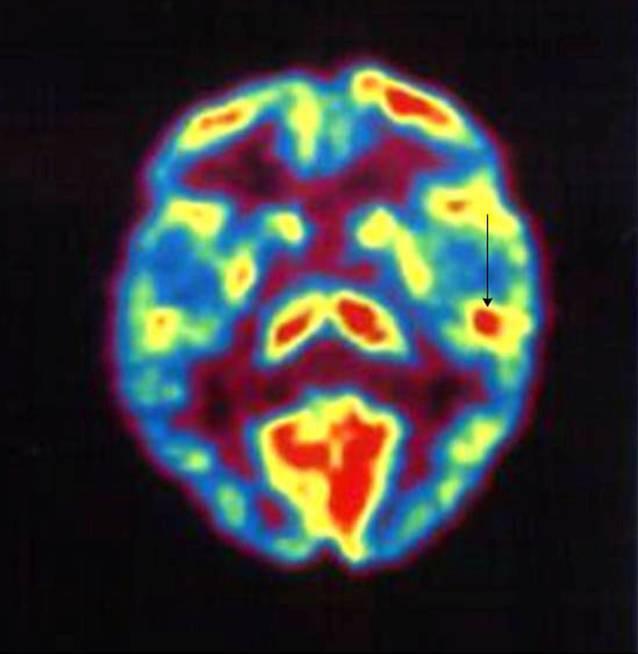

Die PET basiert auf der i.v.-Verabreichung radioaktiver Moleküle, welche am Stoffwechsel beteiligt sind. Durch Nachweis eines hohen Glukoseverbrauchs oder durch einen erhöhten Blutfluss lässt sich ein Rückschluss auf erhöhte Hirnaktivität ziehen (Abb. 3).

In der Tinnitusforschung zeigte sich die PET in der Untersuchung der Hirnaktivität als dienlich. Es wird davon ausgegangen, dass eine periphere Deafferenzierung (z. B. durch periphere Hörschädigung) den Tinnitus auslöst, aber zentrale neuroplastische Prozesse die Wahrnehmung des Geräuschs aufrechterhalten [32]. Zu diesen Prozessen zählen u. a. eine neuronale Hyperaktivität und erhöhte Spontanaktivität im auditorischen Kortex, welche in verschiedenen Tinnitusmodellen Teile der Pathophysiologie sind.

Untersuchungen, bei denen die FDG-PET im Ruhezustand zum Vergleich der relativen Stoffwechselaktivität im linken und rechten primären auditorischen Kortex eingesetzt wurde, ergaben eine signifikant stärkere Asymmetrie bei TinnituspatientInnen als bei Kontrollpersonen, wobei der linke auditorische Kortex eine höhere Ruheaktivität aufwies als der rechte auditorische Kortex [2]. Jedoch wurde in einer neueren Studie keine erhöhte Aktivität in der Tinnitusgruppe festgestellt [9].